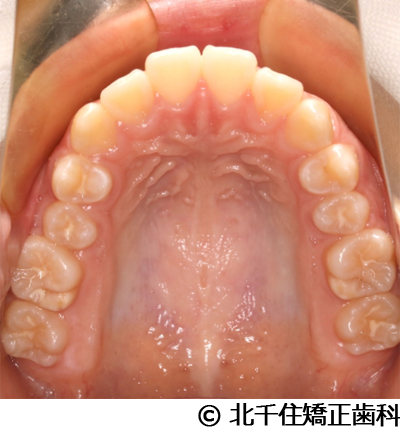

【症例3】叢生

- 治療前

- 治療後

- 治療名

- 叢生

- 費用

- 1,125,000円(税込)

- 期間

- 2年1ヵ月

- 治療回数

- 26回

- 通院頻度

- 1ヵ月ごと

- 年齢・性別

- 19歳3ヵ月・女性(初診時)

治療内容

-

患者様の症状

主訴:デコボコ、口元の突出

治療方法

上下顎第一小臼歯4本を抜歯してワイヤー矯正(セラミックブラケット)。

治療結果

叢生に対し抜歯を併用した矯正治療により、歯列および咬合関係の調整を行った症例である。治療後は保定装置を使用し、歯列および咬合の安定維持を目的として定期的な経過観察を行っている。

※治療結果は個人差があります。

治療を行う上での注意点(リスク・副作用)

歯磨き不良に伴うカリエスや歯周病、歯根吸収など。